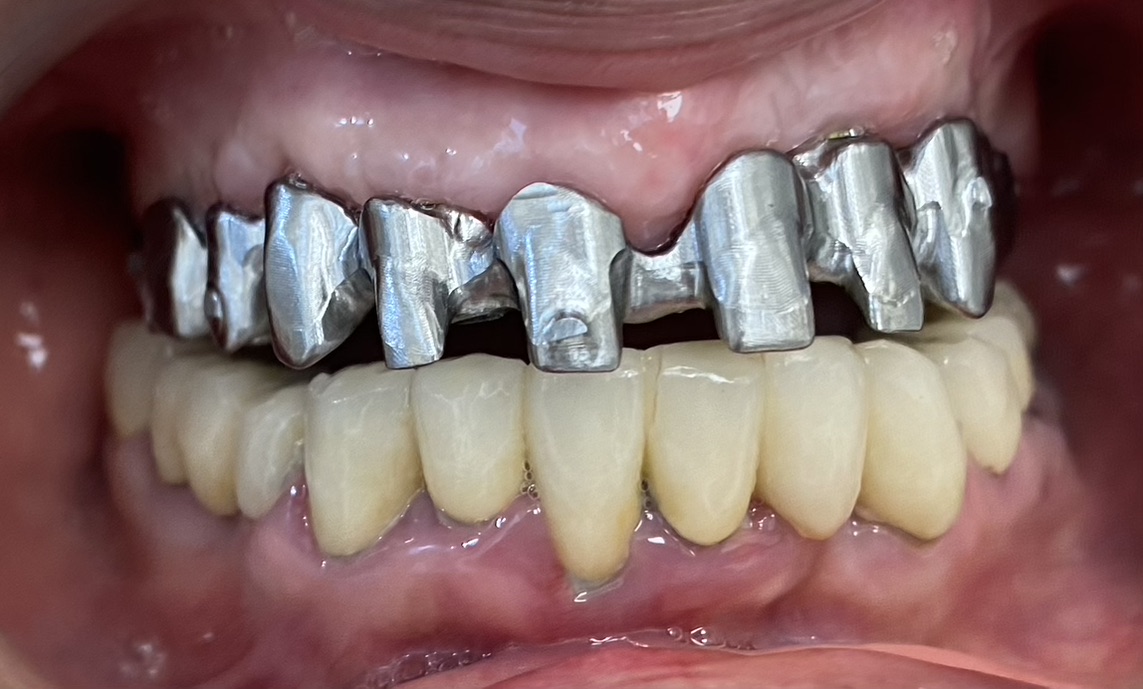

גלריית הצגת מקרים לפני ואחרי